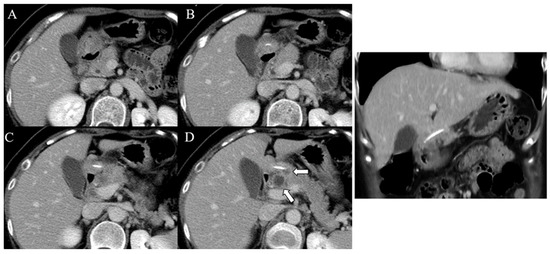

A 49-year-old woman without any underlying conditions presented to our emergency department with worsening dull epigastric pain for over 2 months, general soreness, and fever for 2 days. Physical examination revealed fever up to 39.1 °C with tenderness over the epigastric area; no other complications were reported. Laboratory data indicated a white blood cell count of 8400/µL (neutrophils 88.7%) and a mildly elevated level of C-reactive protein (3.6 mg/dL). The liver function test results and pancreatic enzyme levels were within normal limits. Furthermore, abdominal sonography revealed a small hypoechoic lesion in the hilar area of the liver, and esophagogastroduodenoscopy barely revealed superficial gastritis without mucosal protrusion or ulcer suspiciously indicating the site of foreign body penetration or other etiology. Further investigation was performed through abdominal computed tomography (CT) that revealed a 2.7 cm radiopaque foreign body located between the prepyloric region of the stomach and the pancreatic head and a multiloculated abscess in the pancreatic head and near the aforementioned foreign body (Figure 1). The patient recalled swallowing a piece of fish bone accidentally 2 months prior. Gastric perforation with pancreatic abscess secondary to the fish bone penetration injury was suspected. Considering the length of the fish bone, extraluminal migration, and concurrent multiloculated pancreatic abscess, she was admitted to the hospital and received laparoscopic surgery for removal of the fish bone. The intraoperative findings were a 4 cm long fish bone penetrating through the posterior wall of the gastric antrum into the pancreatic head (Figure 2B,C) and adjoining the pancreatic abscess, and a severe adhesion between the distal stomach and liver, which was identified (Figure 2A) and removed through adhesiolysis. Antibiotic treatment was administered for postoperative symptomatic and supportive treatment. The patient recovered well and was discharged on the seventh postoperative day. No complications were noted in a subsequent health checkup 1 year after the operation.

Figure 1. Contrast-enhanced CT imaging with serial sections in the axial (AD) and coronal planes displaying a linear and hyperdense foreign body penetrating through the posterior wall of the gastric antrum into the pancreatic head. The white arrows indicate abscess formation in the pancreatic head and near the ingested foreign body.